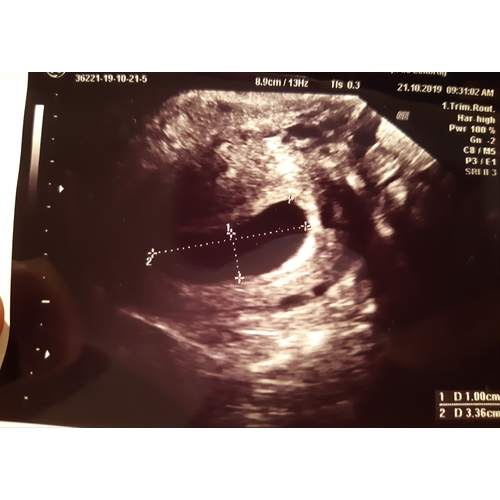

Gisteren ook eerste echo gehad waar een leeg vruchtzakje te zien was dat nog maar 1cm is, wat overeenkomt met 4 weken. Volgens eigen berekening zou ik 7 weken zijn. Meteen na consultatie naar labo geweest voor een bloedname en morgen weer een bloedname om te zien of HCG verdubbeld is.